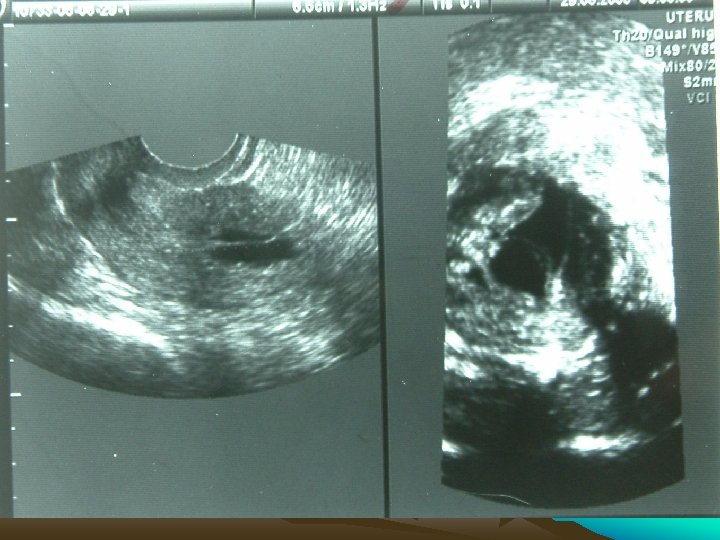

Investigations • • • Chest X Ray USG CECT EUS Ba Swallow 3

Present Complaints • Bleeding P/V x 2 months (July 2005) • Hematemesis, Wt loss • GPE N

Bleeding PV • All causes + • Tamoxifen induced hyperplasia, polyp, carcinoma, • Mets from Metastatic Lobular breast CA

Tx►Polyps► hyperplastic or metstatic • Hysteroscopy is mandatory

Tamoxifen ► Post M Bleed P/V ►Hysteroscopy mandatory Taponeco F, Curcio C, Fasciani A, Giuntini A, Artini PG, Fornaciari G, et al. Indication of hysteroscopy in tamoxifen treated breast cancer patients. J Exp Clin Cancer Res. 2002 Mar; 21(1): 37 -43 Malignancy in 7. 8%+ 4% premalignant lesions in Postmenopausal Tx ► 3 y

Provisional diagnosis • Bleeding PV- Tx induced polyp • Mets from Metastatic Lobular breast Ca • Her 2 neu related endometrial cancer

Diagnosis • Polyp / Metastases of Lobular Breast CA in Ut • GIST, Lymphoma / 2 nd primary at GI jn